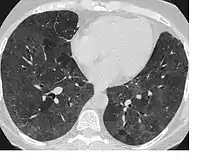

CT image showing mosaic attenuation pattern in patient with hypersensitivity pneumonitis. Note the alternating, patchy areas of increased and decreased attenuation, particularly in the left lung (screen right).

Mosaic

A mosaic pattern of GGO refers to multiple irregular areas of both increased attenuation and decreased attenuation on CT. It is often the result of occlusion of small pulmonary arteries or obstruction of small airways leading to air trapping.[6] Sarcoidosis is an additional cause of a mosaic GGOs due to the formation of granulomas in interstitial areas. This may coexist with granulomatosis with polyangiitis, leading to diffuse areas of increased attenuation with ground-glass appearance.[6]